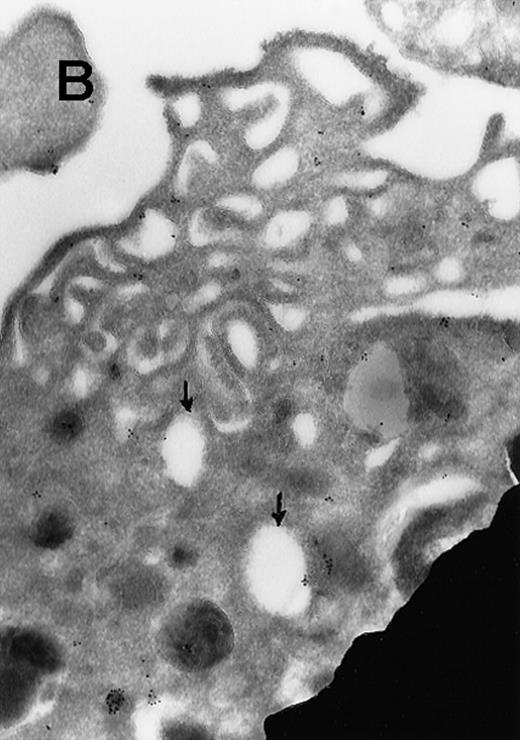

In view of these reports, we determined the cellular localization of MAP kinase in megakaryocytes, with a particular attention to the platelet-yielding demarcation membranes.7As a control, we determined the localization of another TPO-upregulated serine/threonine kinase, Mst1.8 Our current Electron Microscopic (EM) studies, performed as we described before,9 reveal that a significant fraction of MAP kinase, but none of Mst1, localizes to the demarcation membranes. In resting platelets, MAP kinase is found in a cluster pattern associated with the plasma membrane (which is believed to originate from the megakaryocytic demarcation membranes),7 as well as over electron-dense cytoplasmic domains (Figure). In view of our finding that MAP kinase is localized to the demarcation membranes in megakaryocytes, it is of interest to note that this kinase was also shown to be localized in Golgi membranes and involved in their fragmentation during mitosis in a microtubule-dependent manner.10 Platelet fragmentation likely involves the cytoskeleton, and perhaps MAP kinases are also involved in this process.

(A) Ultrathin frozen sections of rat platelets immunolabeled with antibodies to ERK (magnification ×45 000). (B) Well-developed demarcation membranes in a rat (Wistar), TPO-treated megakaryocyte7 9 immunostained with an antibody to Mst1 (magnification ×48 000), or (C) with an antibody to ERK, which recognizes ERK1 and ERK2 (magnification ×65 400). The arrows point to the demarcation membranes. The Mst1 antiserum (gift of Dr Jonathan Chernoff, Fox Chase Cancer Center, Philadelphia, PA) and anti-ERK2 (K-23) (Santa Cruz Biotechnology, Santa Cruz, CA) or TR2, anti-ERK (gift of Michael Weber, University of Virginia Medical School) were diluted 1:10.

(A) Ultrathin frozen sections of rat platelets immunolabeled with antibodies to ERK (magnification ×45 000). (B) Well-developed demarcation membranes in a rat (Wistar), TPO-treated megakaryocyte7 9 immunostained with an antibody to Mst1 (magnification ×48 000), or (C) with an antibody to ERK, which recognizes ERK1 and ERK2 (magnification ×65 400). The arrows point to the demarcation membranes. The Mst1 antiserum (gift of Dr Jonathan Chernoff, Fox Chase Cancer Center, Philadelphia, PA) and anti-ERK2 (K-23) (Santa Cruz Biotechnology, Santa Cruz, CA) or TR2, anti-ERK (gift of Michael Weber, University of Virginia Medical School) were diluted 1:10.